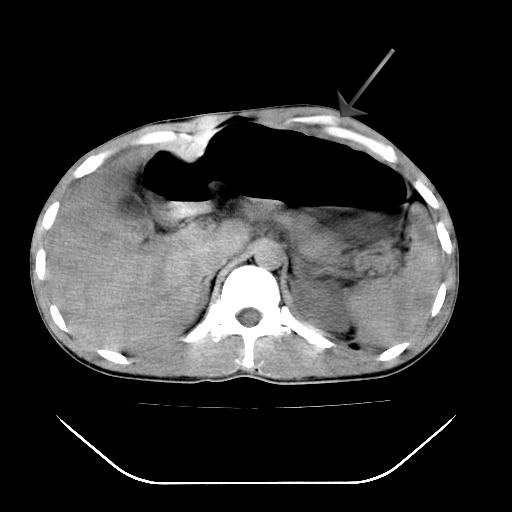

结果收到,谢谢楼主,另外反过来看这个地方是不是游离气体影

胃大弯侧是否在5号就已经有游离气体了?